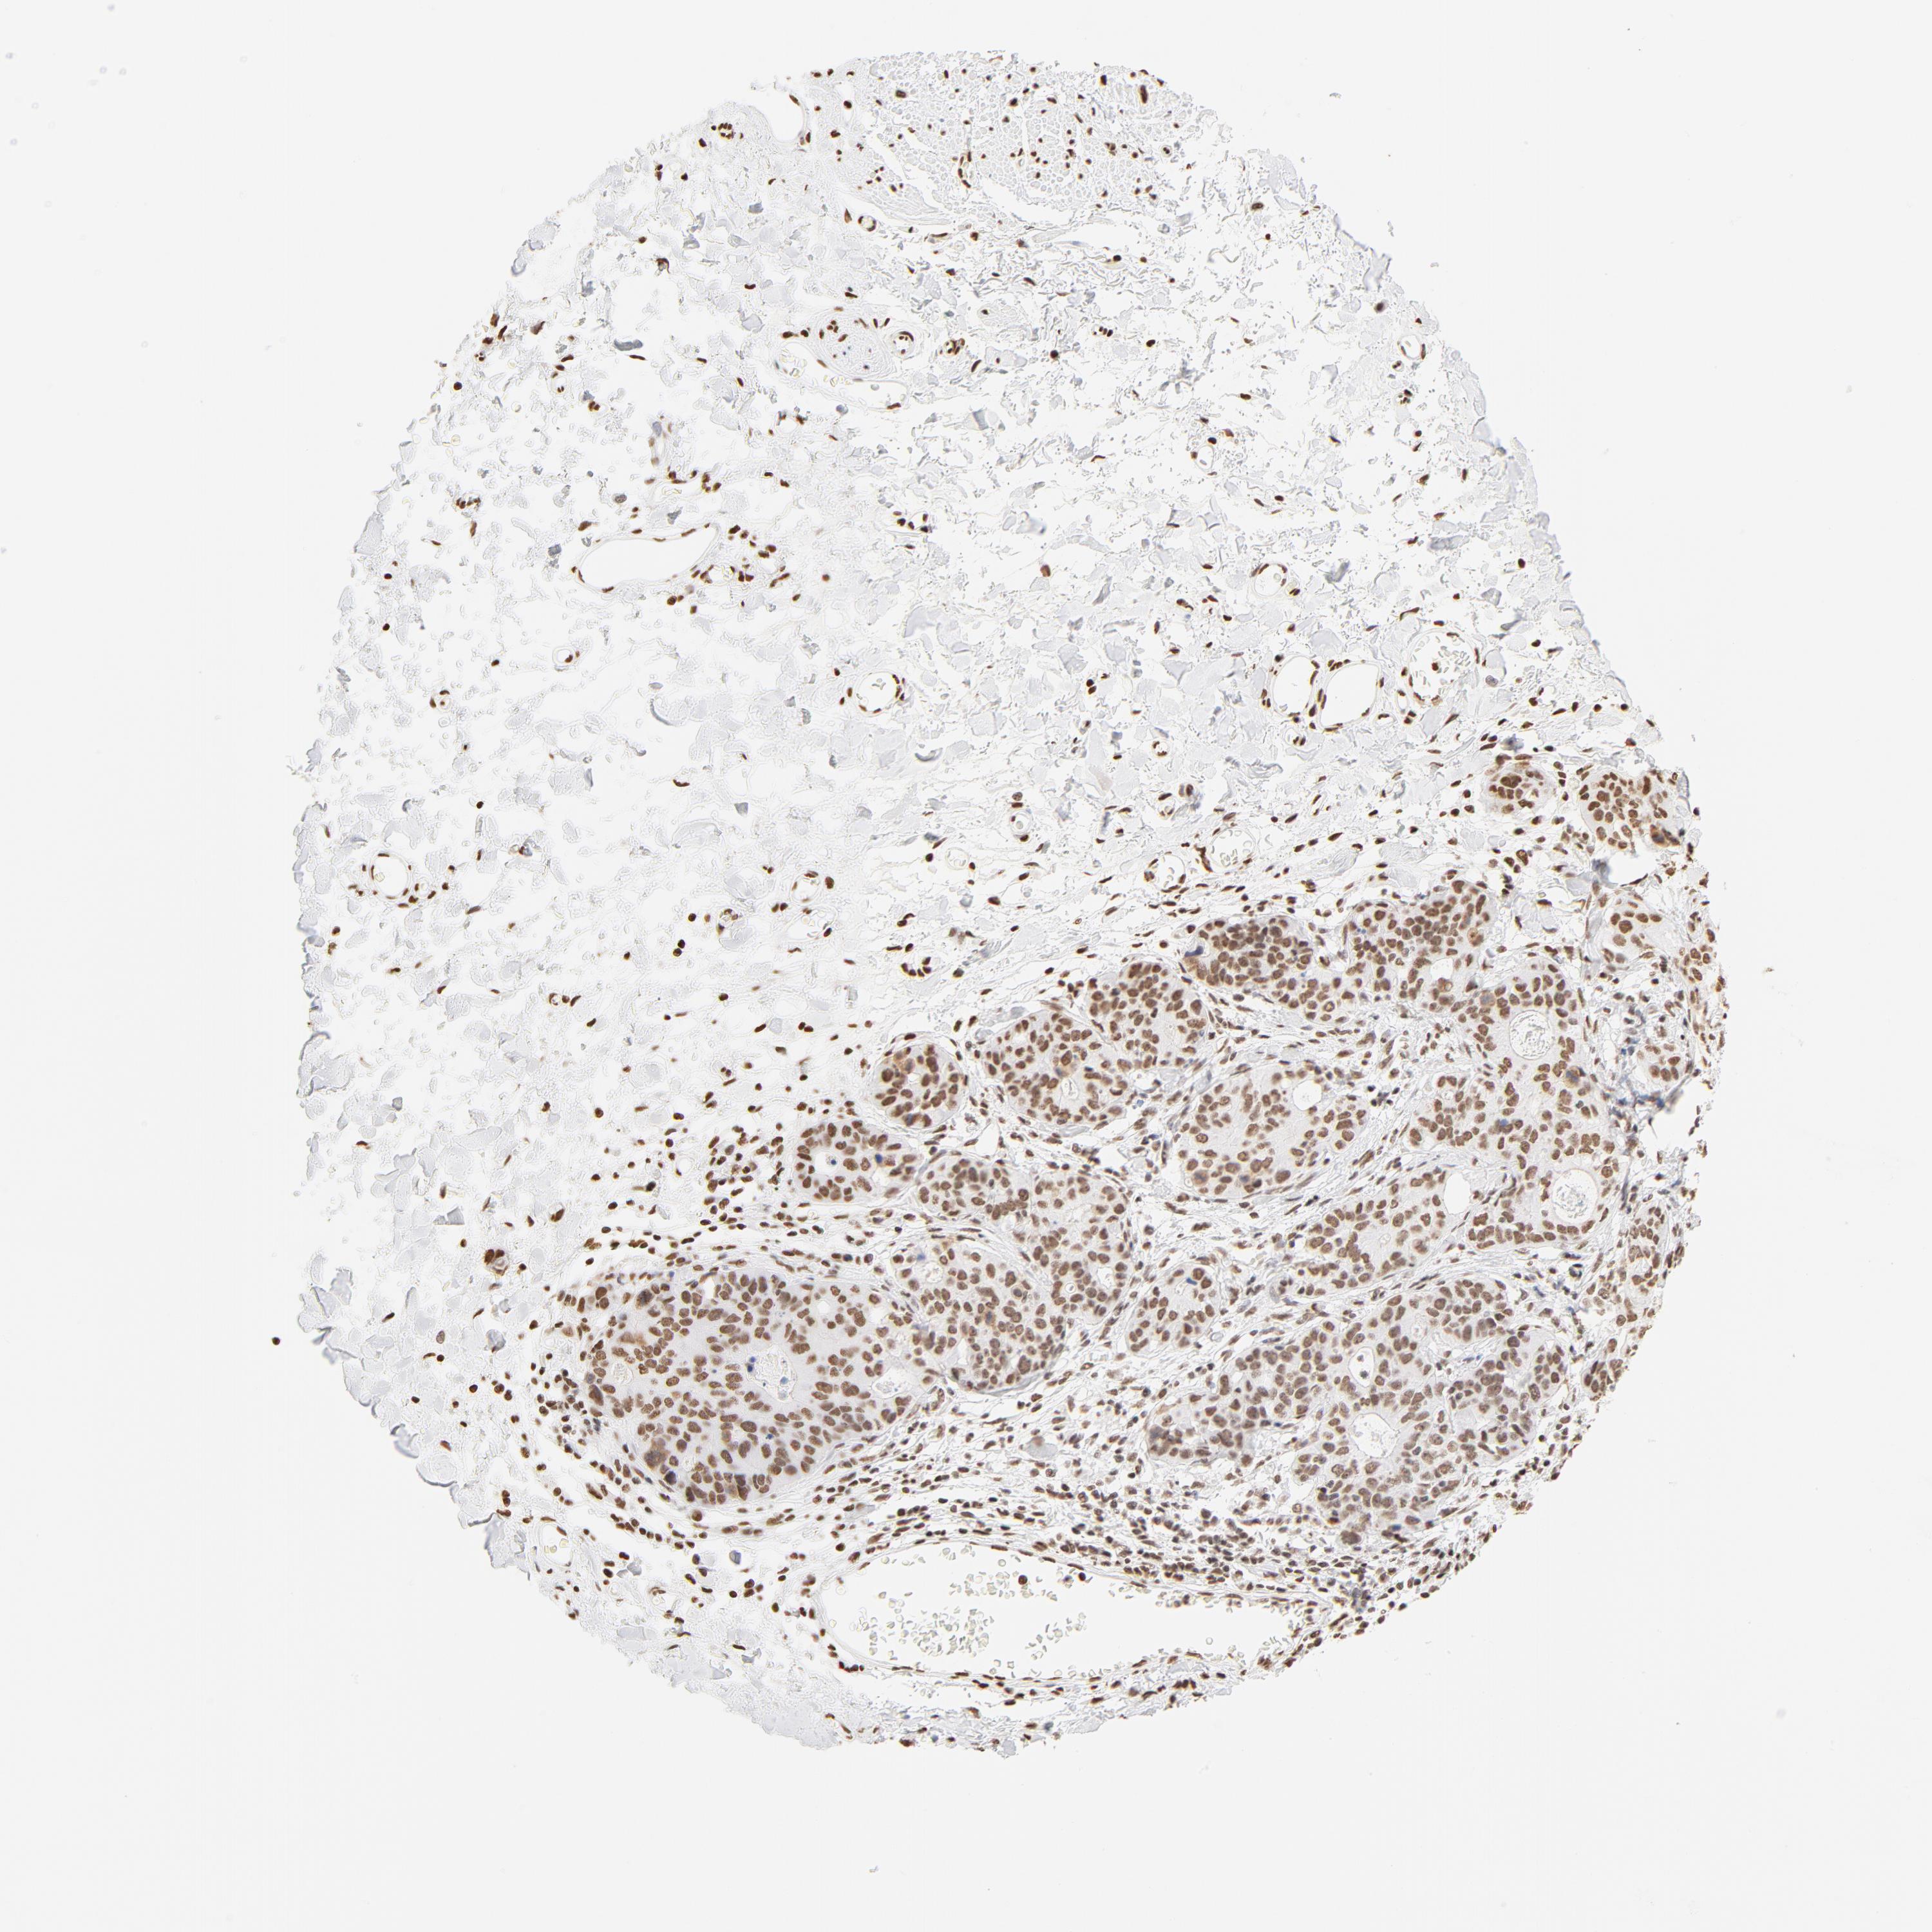

STOMACH CANCER - Protein expressioni

A mouse-over function shows sample information and annotation data. Click on an image to view it in a full screen mode. Samples can be filtered based on level of antibody staining by selecting one or several of the following categories: high, medium, low and not detected. The assay and annotation is described here.

Note that samples used for immunohistochemistry by the Human Protein Atlas do not correspond to samples in the TCGA dataset.

Antibody stainingi

Antibody staining in the annotated cell types in the current human tissue is reported as not detected, low, medium, or high, based on conventional immunohistochemistry profiling in selected tissues. This score is based on the combination of the staining intensity and fraction of stained cells.

Each image is clickable and will lead to virtual microscopy that enables deeper exploration of all samples and also displays staining intensity scores, fraction scores and subcellular localization as well as patient and tissue information for each sample.

Antibody HPA003444

Staining

High

Medium

Low

Not detected

Intensity

Strong

Moderate

Weak

Negative

Quantity

>75%

75%-25%

<25%

None

Location

Nuclear

Cytoplasmic/membranous

Cytoplasmic/membranous,nuclear

Adenocarcinoma, NOS